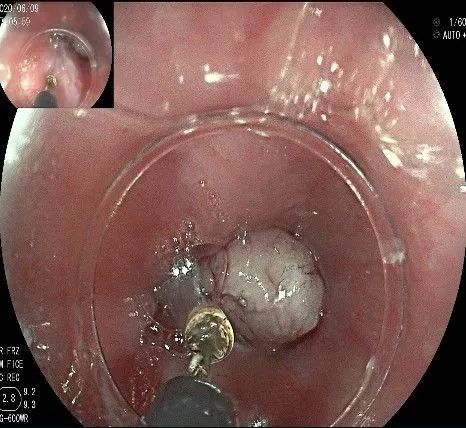

此时瘤体基底部已暴露出来,起源于固有肌层。

这是最后的“根”部。

换用IT刀可以轻松剥离,又避免切入过深造成穿孔。